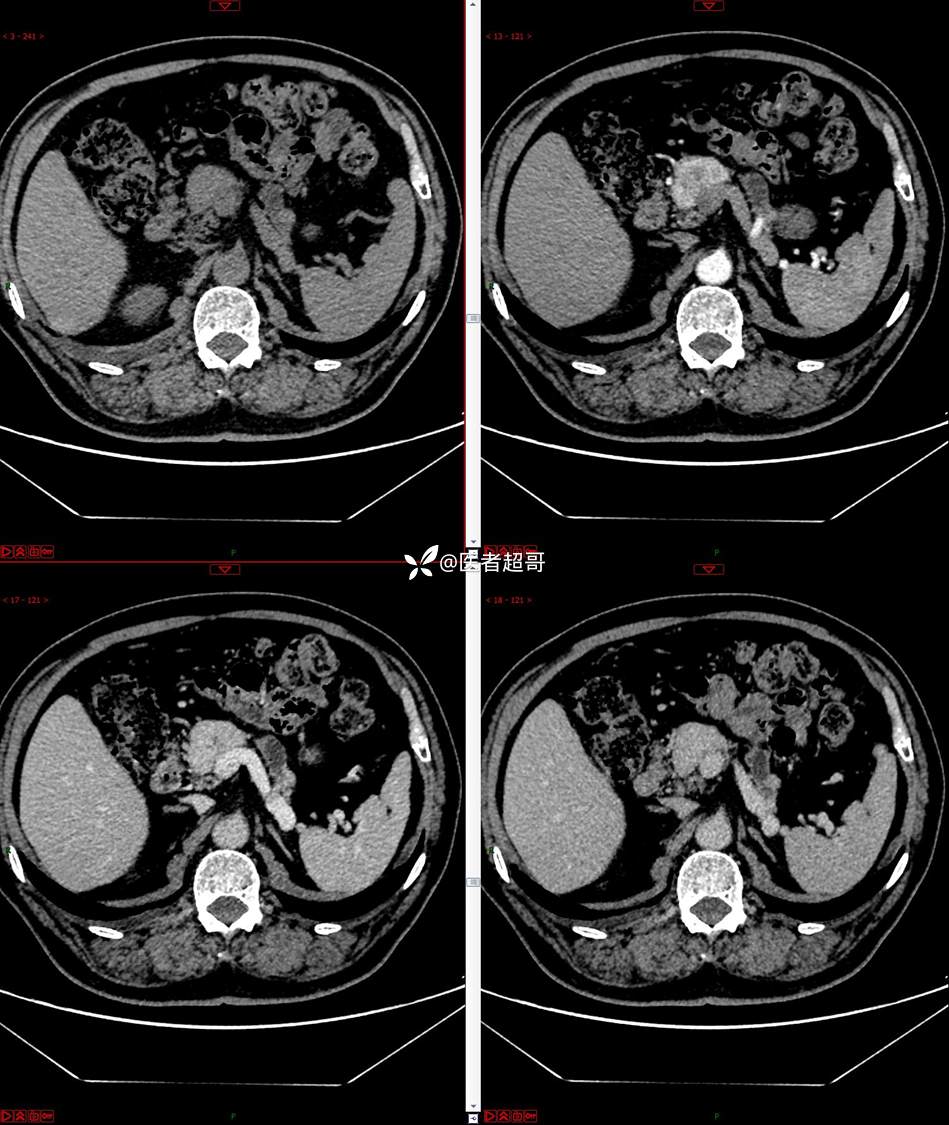

【影诊笔记677】查体发现胰腺占位性病变1周,细节决定成败,请诊断分析!

主 诉:查体发现胰腺占位性病变1周。

现病史:患者1周前在当地查体时发现胰腺占位性病变,无恶心、呕吐,无腹痛,无寒战、高热,无咳嗽、咳痰等异常不适,来我院门诊查上腹部CT平扫+强化:胰腺尾部异常密度灶。今为求进一步治疗,门诊以“胰腺占位性病变”收入院。患者自发病以来,一般情况可,神志清,精神可,普通饮食,二便正常,体重及体力无明显改变。

既往史:既往糖尿病病史2年,口服二甲双胍早晚各一片和格列吡嗪早晚各一片,否认高血压、心脑血管病等疾病史,否认肝炎、结核或其他传染病史及密切接触史,预防接种史不详,否认药物及食物过敏史,否认外伤史,12年前肾癌切除术手术史,否认输血史,其它无特殊。